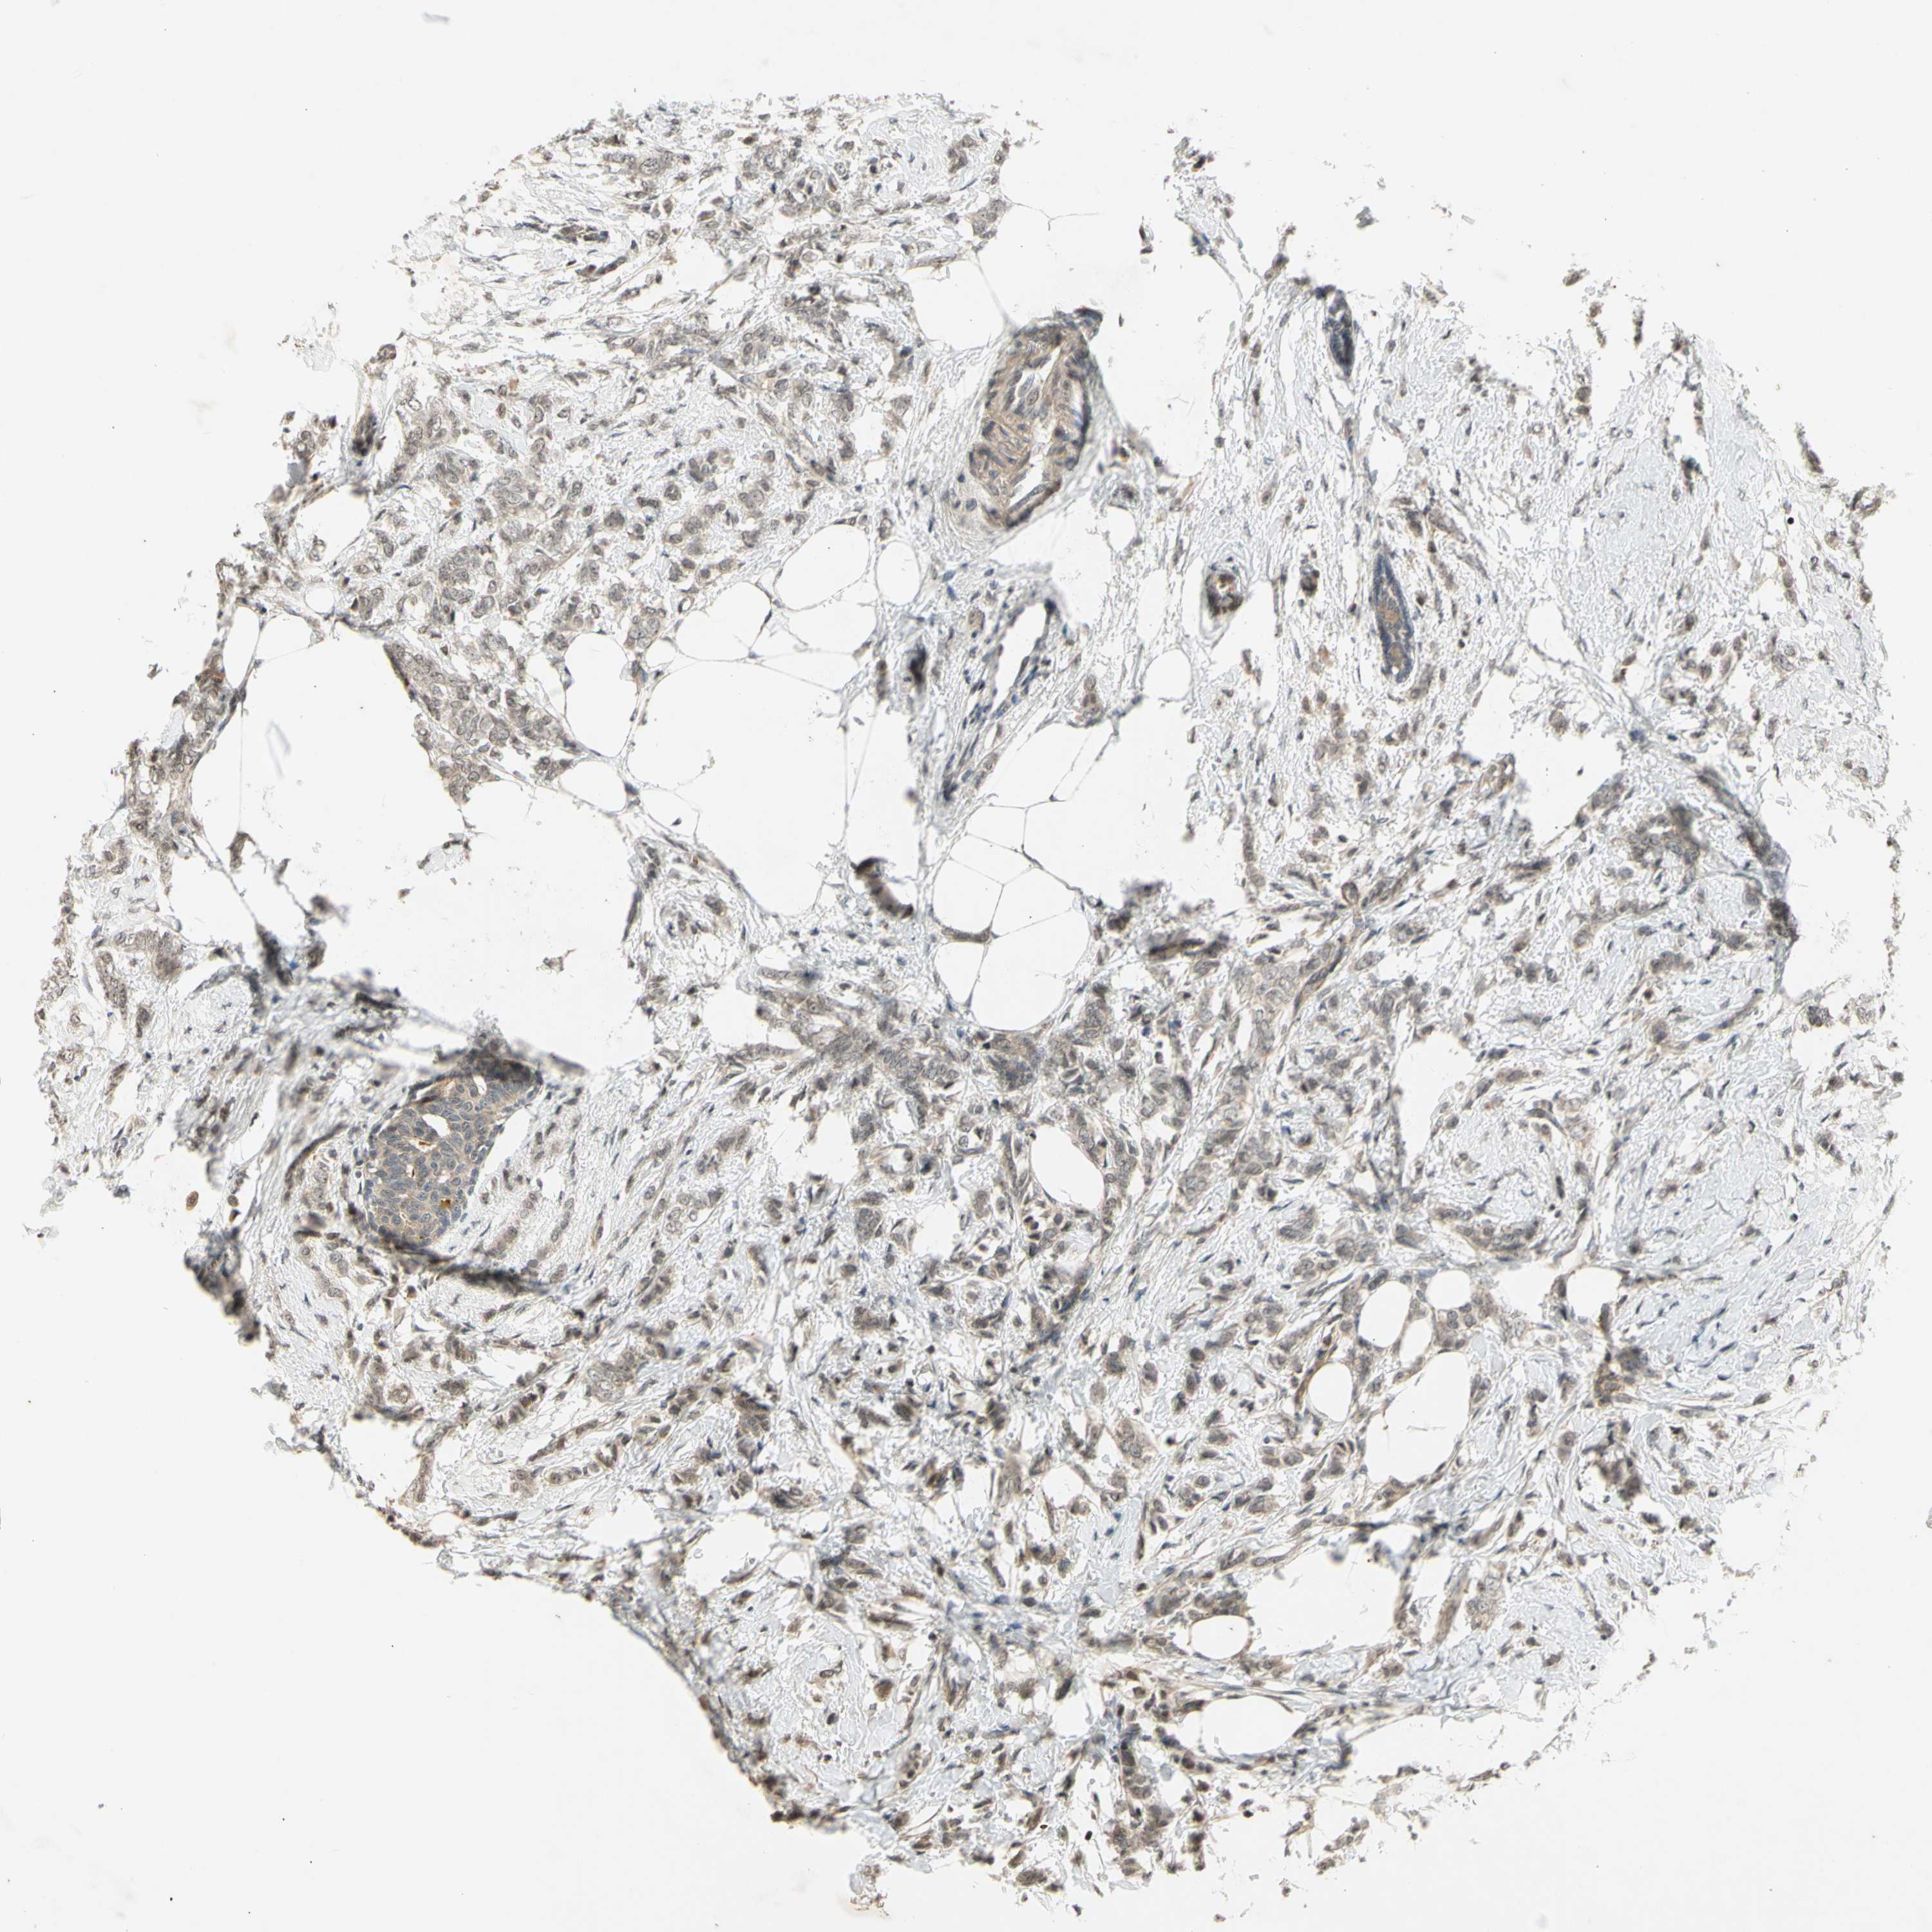

CANCER BREAST CANCER Show tissue menu

Breast cancer

Human cancer